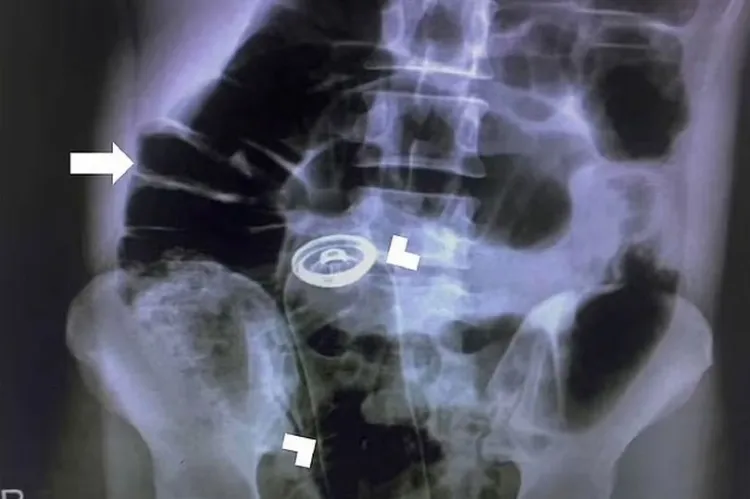

Un pacient s-a prezentat la spital cu un spray în organism, iar medicii l-au operat de urgență - FOTO

Medicii au fost nevoiți să opereze de urgență cun bărbat care avea un spray blocat în anus. Chirurgii au intervenit pe la nivelul stomacului, neavând altă variantă la dispoziție.

Bărbatul de 30 de ani s-a dus singur la urgență, după ce și-a introdus singur un spray în anus. Acesta a încercat să rezolve singur problema acasă, dar fără sorți de izbândă, așa să medicii au fost singura soluție.

Medicii nu au vrut să riște și să deterioreze mai mult anusul, așa că au intervenit chirurgical prin stomac, relatează Daily Star.

Operația a avut loc în aripa de urgență cadrul Universității de Științe Medicale din Teheran, iar pacientul a fost externat după 24 de ore.